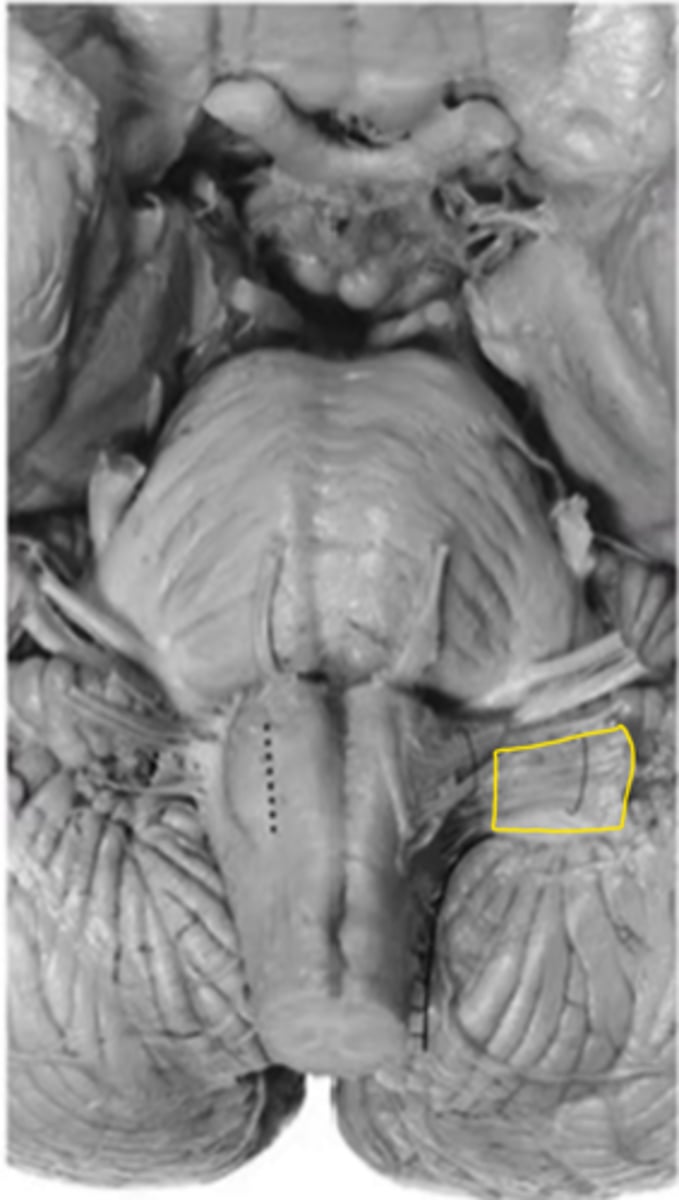

medulla

ID the area

medullary pyramids

ID the structure

anterior median sulcus

pyramidal decussation

olive

pre-olivary sulcus

vestibulocochlear nerve

ID the nerve

glossopharyngeal nerve

vagus nerve

hypoglossal nerve

spinal accessory nerve

fourth ventricle

ID the space

open medulla

closed medulla

ID the brainstem level